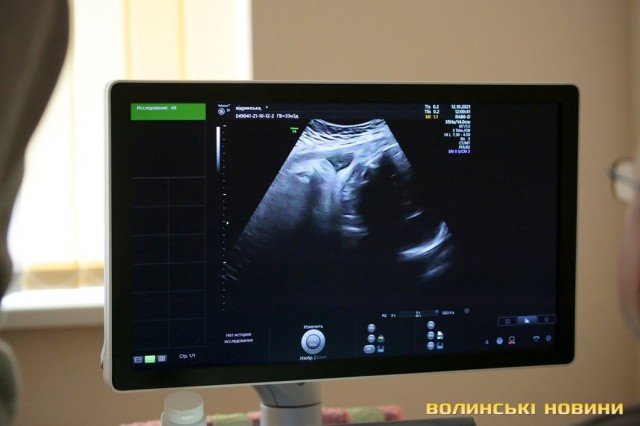

Волинський обласний перинатальний центр закупив найкращий УЗД-апарат з акушерської діагностики у світі – «Voluson E8BT21».

Відтепер лікарі зможуть краще дослідити плід, адже новий апарат має функції 3D, 4D, Real time 4D та автоматичні програми з визначення анатомічних розмірів плода. А самі спеціалісти кажуть, що ніколи не бачили майбутню дитину так детально.

«Таких апаратів в Україні є лише три: два в Києві і тепер у Луцьку. Цей апарат найвищого рівня – Expert. Він має такі функції - 3D, 4D, Real time 4D, автоматичні програми з визначення анатомічних розмірів плода. В сучасних апаратах з’являється і штучний інтелект, коли машина може сама визначати, де лобно-потиличний розмір, шлуночок, велика цистерна. Але це все одно контролює людина. Апарат також обладнаний автоматичними програмами для дослідження серця. За рахунок того, що він обладнаний технологією Volume analysis calculation, є можливість отримати дослідження, які за допомогою 2D-сканування неможливо було би поміряти і відрізнити. Це безпрецедентно, що в Луцьку з’явився апарат такого рівня», – наголосив Максим Рудой.

«Дуже важко описати враження. Ми щойно оглядали пацієнтку, картинка дуже відрізняється від тієї, яка була на попередніх апаратах УЗД. Я ще ніколи не бачив плід так детально, як на цьому апараті, це, зокрема, обличчя, внутрішні органи. На попередніх апаратах це неможливо було зробити. Тепер я можу більш детально описати стан майбутньої дитини. Можливості апарата дуже широкі для перинатальної діагностики. В ультразвуковій діагностиці важливі дві речі: спеціаліст та хороше обладнання. Обладнання ми точно маємо та й кажуть, що Грибчук – непоганий спеціаліст», – скромно розповідає лікар.